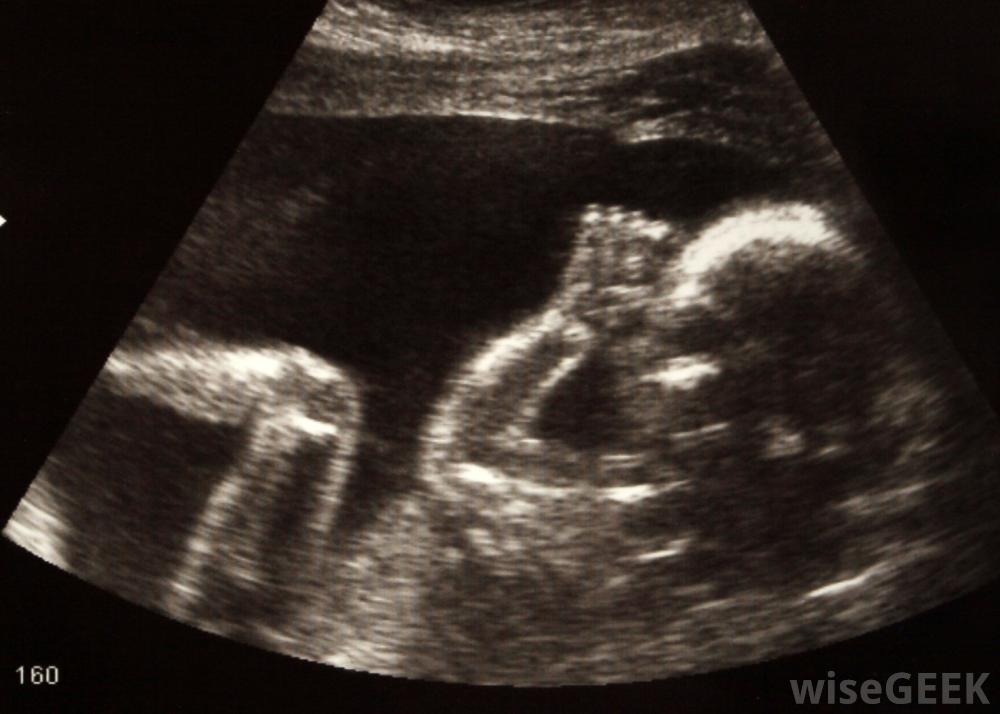

超声波可用于检查胎儿发育。

产前超声检查。

超声照片有助于让怀孕的夫妇真正怀孕。